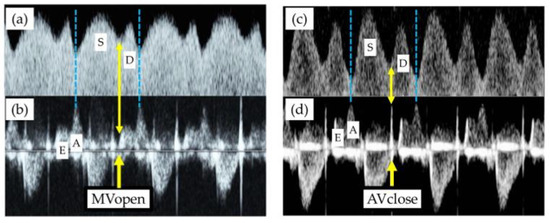

4.2. Representative Alterations in Doppler Measurements of Ductus Venosus in FGR